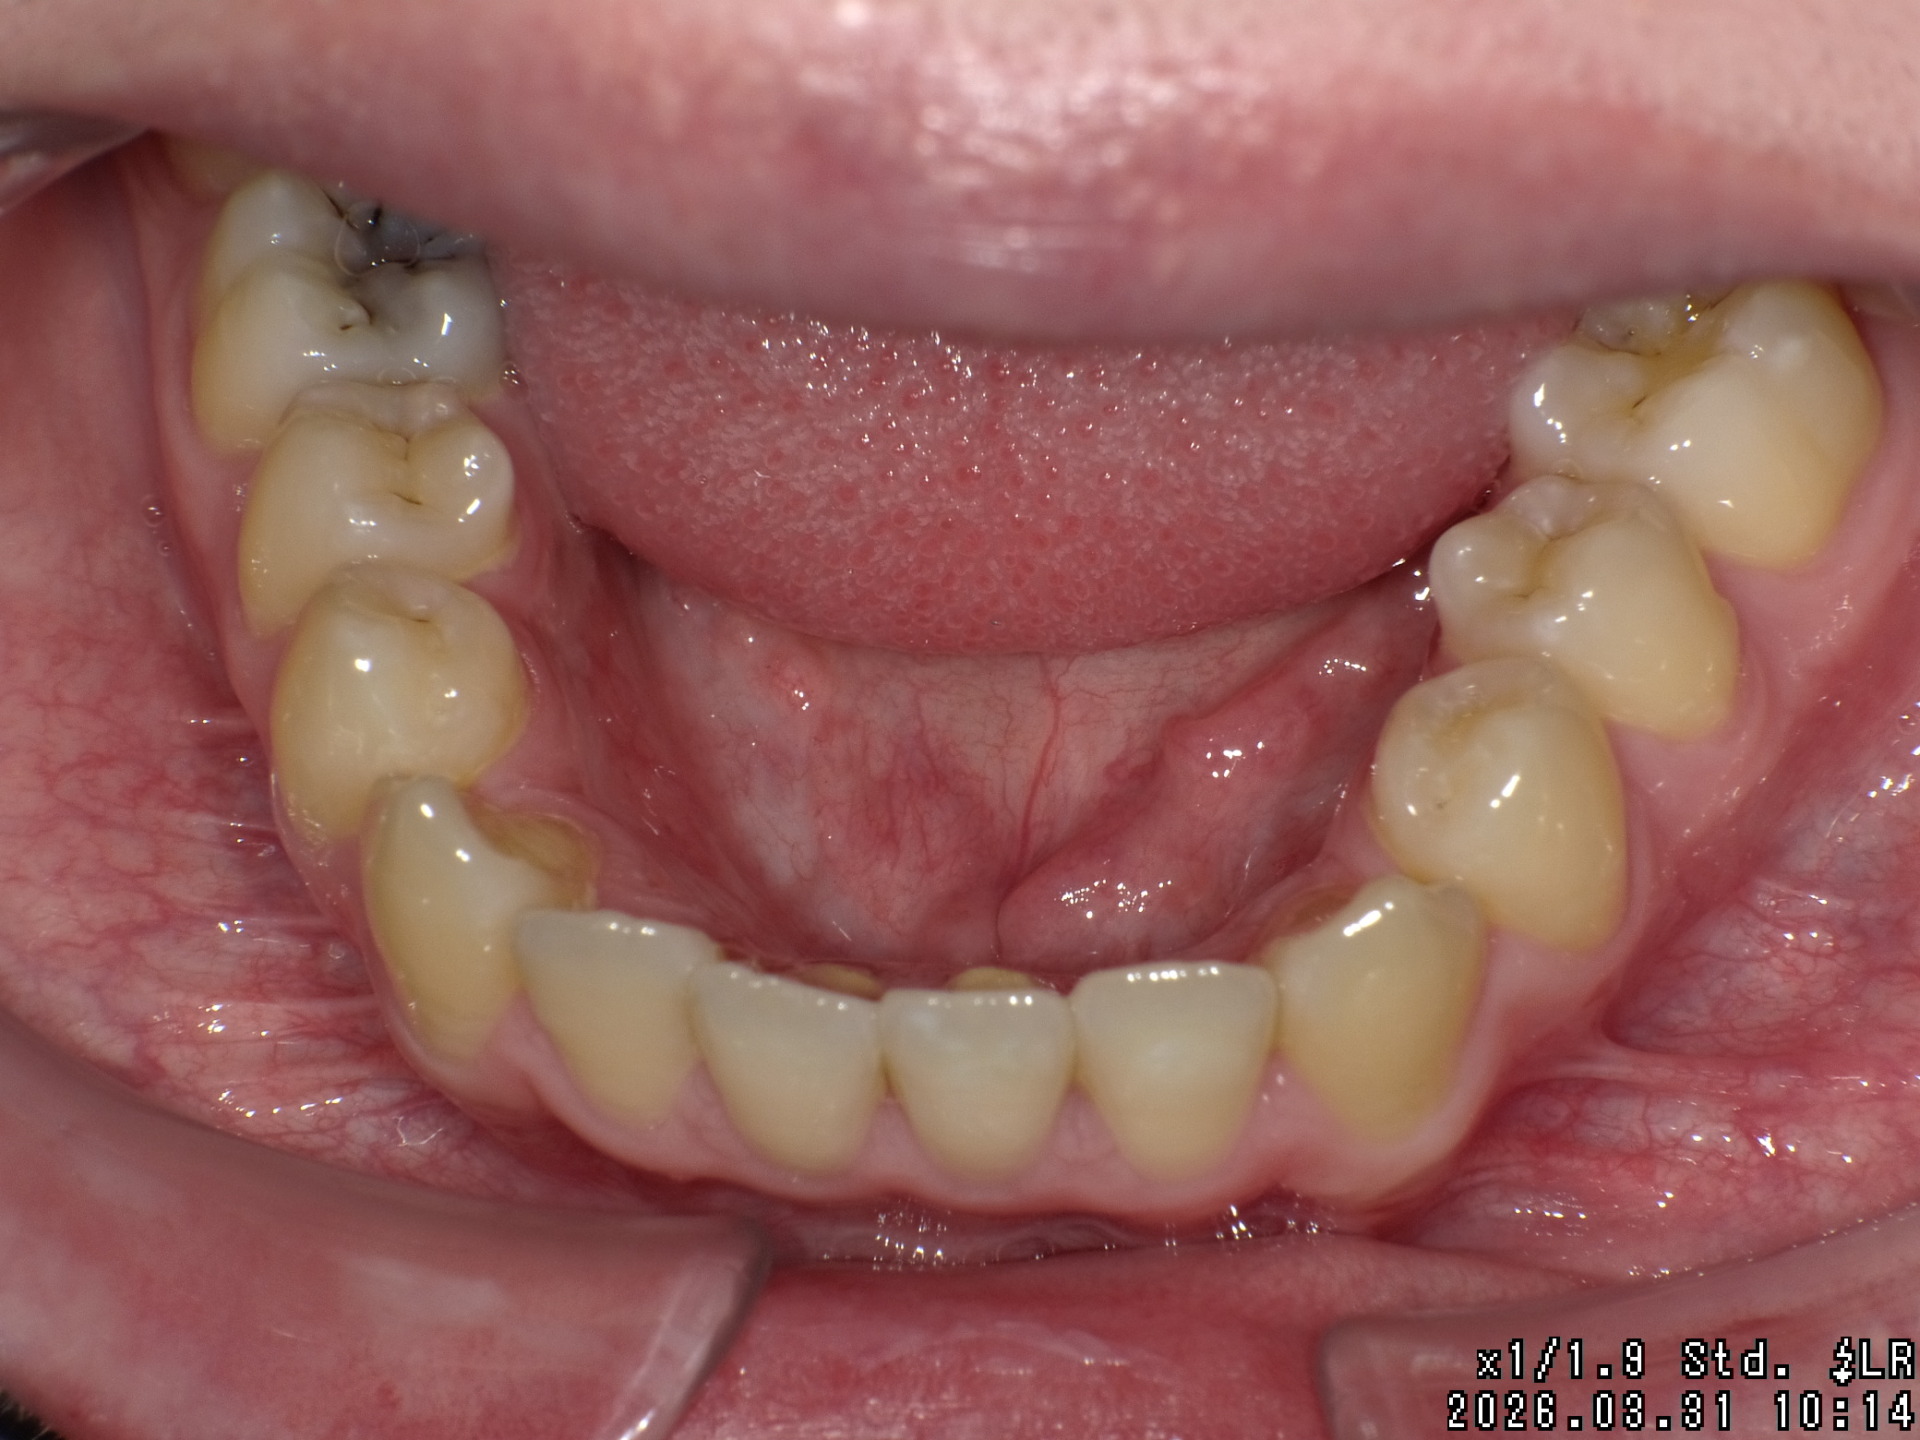

After

| 症状 | 右上八重歯 上顎正中の著しいずれ |

| 処置内容 | ディスタライザー・マルチブラケット装置 |